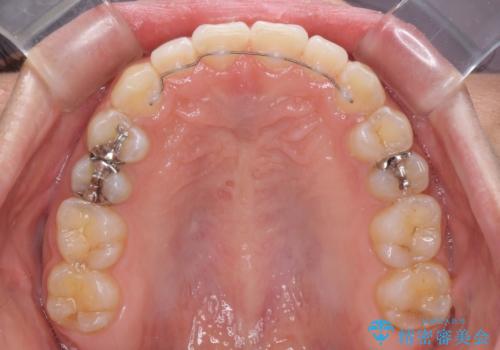

前歯の隙間を閉じたい 短期間でのワイヤー矯正

下の前歯が上の前歯を突き上げるように咬合するため、咬み合わせの位置を改善しながら隙間を閉じていきました。

元々の歯並びが悪くなかったため、9ヶ月で綺麗に仕上がりました。

すきっ歯は後戻りを起こしやすいため、上下ともに歯の裏側を細いワイヤーで固定した上で、リテーナーのマウスピースを装着していただいています。